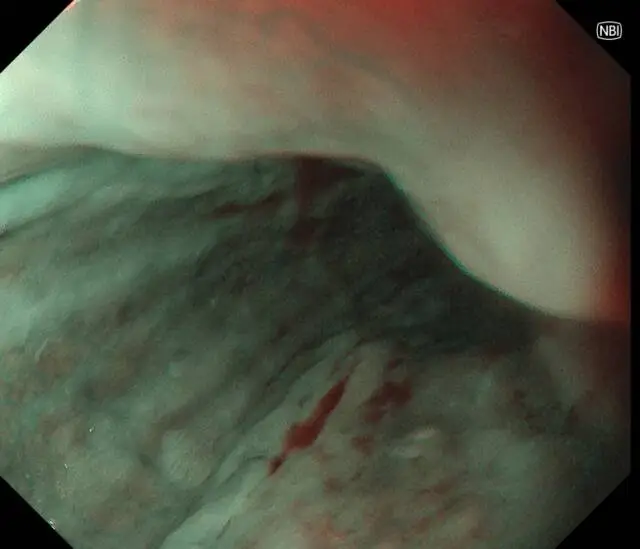

精查发现 外院漏诊隐匿早癌

患者李先生(化名),60多岁,平日不抽烟不喝酒,无任何消化道症状,但有家族史,在子女的带领下来做胃肠镜精查。前两年刚做过胃肠镜,未发现异常。在新镜界精查中,发现胃角处有一黏膜与正常略微不同,经NBI+放大内镜放大观查,考虑胃早癌,活检证实为高级别上皮内瘤变。恰逢麻兴华教授(新镜界日方特聘专家)来院坐诊,于是由麻教授带领内镜团队行内镜下黏膜剥离术(ESD),术后患者痊愈。

因为是早期胃癌,在内镜下行黏膜剥离术(ESD),就能够治愈,无需外科手术及放化疗。这是不幸中的万幸,患者今后只需定期胃镜复查即可。